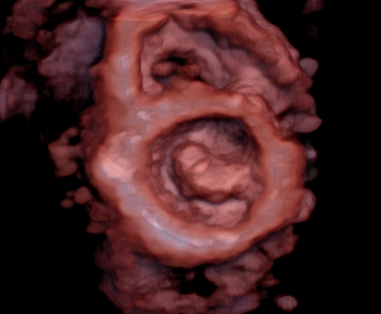

3D echocardiografie geeft een veel gedetailleerder en completer beeld van het hart dan traditionele 2D echocardiografie. In plaats van alleen beelden van het hart in zijaanzicht of bovenaanzicht te tonen, kunnen we nu de interne structuren van het hart vanuit verschillende hoeken bekijken en zelfs 'virtueel' door het hart heen kijken.

Als laatst wordt 3D echocardiografie al langere tijd toegepast bij de analyse van de oorzaak van hartklepafwijkingen. Met name bij slokdarmechocardiografie, maar ook bij transthoracale echocardiografie (als de beeldkwaliteit het toelaat) kunnen 3D beelden van de hartklep worden gemaakt. Dit helpt de cardioloog en de hartchirurg om beter te begrijpen waarom een hartklep lekt en hoe dit gerepareerd zou kunnen worden. Daarnaast worden er steeds met klepingrepen via de bloedvaten in de lies uitgevoerd. Deze ingrepen worden begeleid middels slokdarmechocardiografie en hierbij kunnen we inmiddels niet meer zonder de 3D beeldvorming.